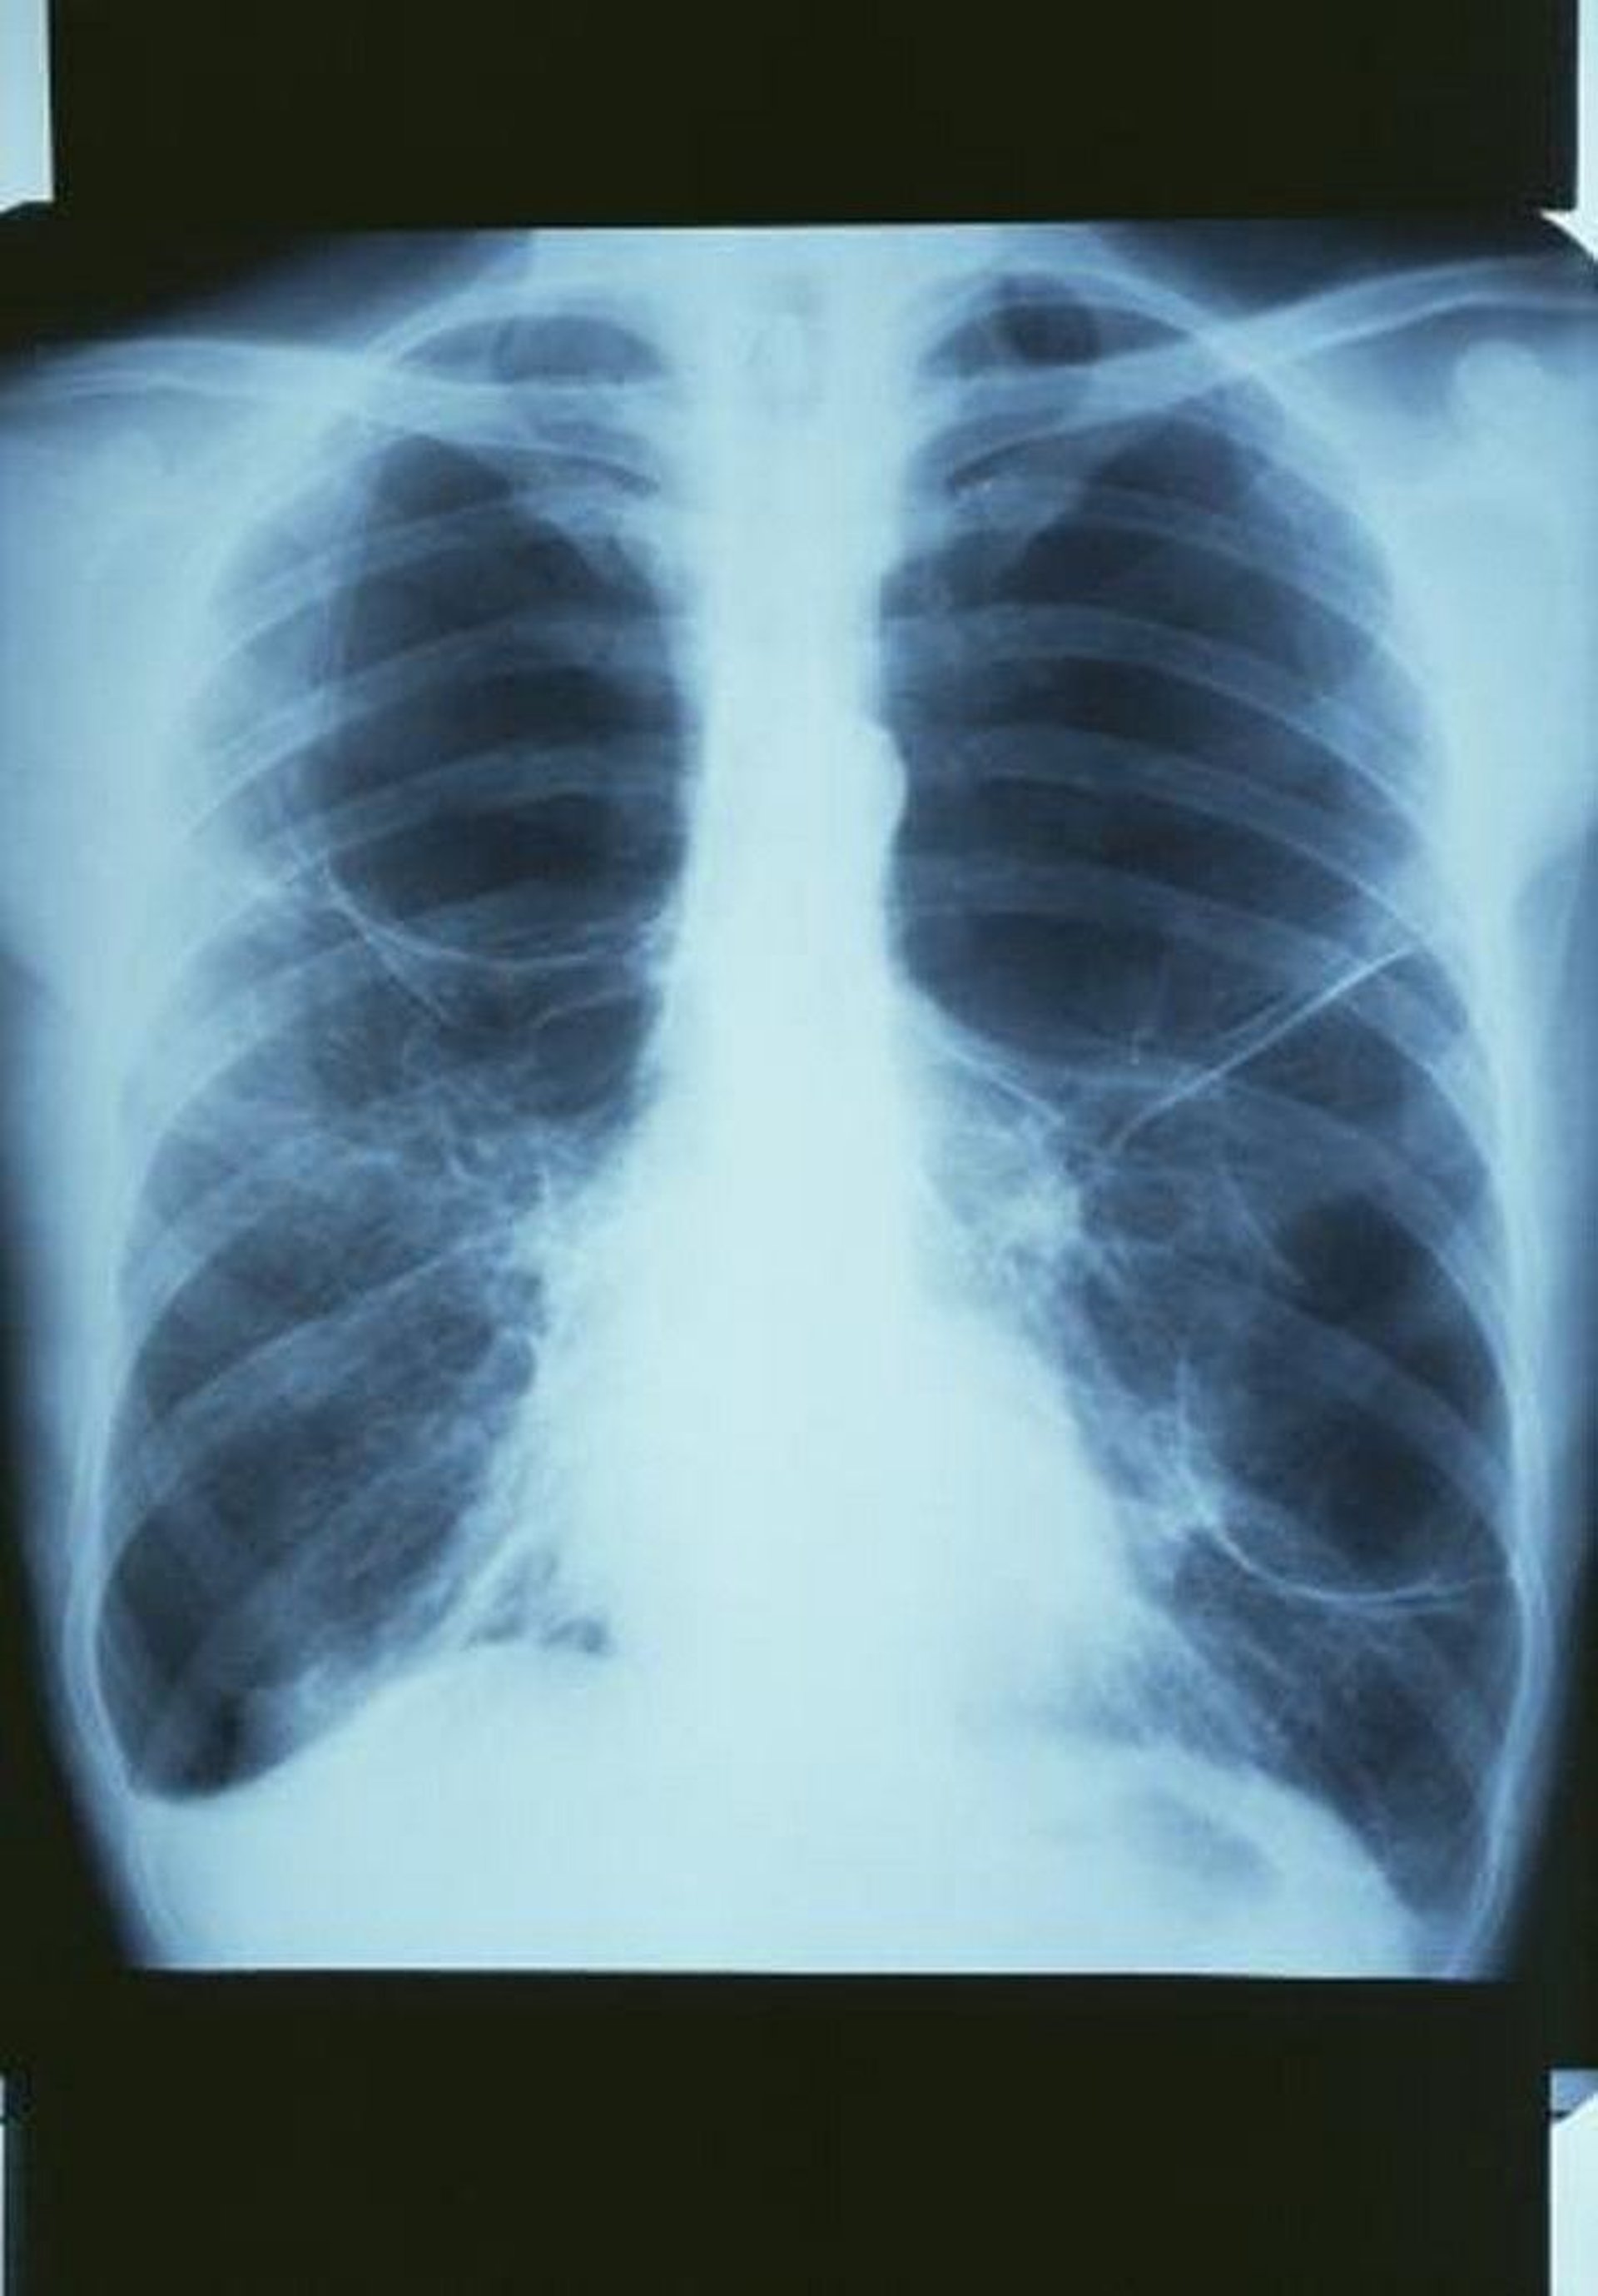

COPD with Bullae

This chest radiograph shows a large bulla in the upper right lung and 2 large bullae in the left lung.